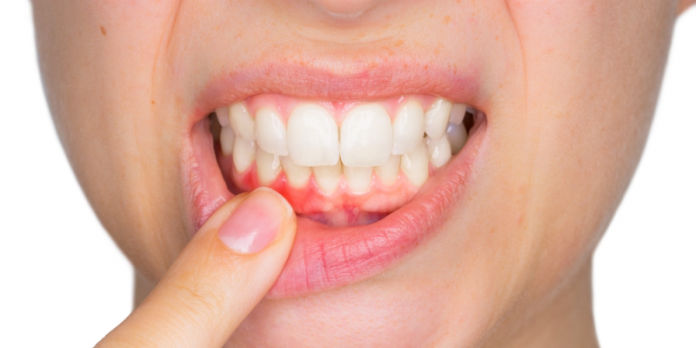

Recessão gengival é uma condição bastante comum entre pacientes de ambos os sexos e em diferentes idades, aumentando sua frequência com o passar dos anos. As maiores queixas dos pacientes com recessão gengival são hipersensibilidade radicular e aspecto antiestético.

A cobertura total das raízes por tecidos gengivais espessos e saudáveis é indispensável para eliminar esses sintomas severos. No entanto, é de grande importância o conhecimento de suas técnicas, indicações e contraindicações, a partir das considerações anatômicas de cada caso.